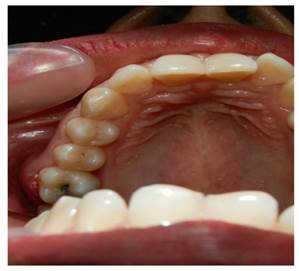

Presentación Caso 3

Paciente femenino de 21 años que acude a consulta odontológica por control el día 10 de enero de 2019; no reporta consumo de medicamentos o antecedentes médicos u odontológicos de importancia. Al examen clínico se evidenció presencia de C en órganos dentarios superiores e inferiores y presencia de BP en órganos dentarios 16 y 17. Radiográficamente no se observa ningún hallazgo de importancia. (Figura 3)

Figura 3. Vista clinica de papila interdental en órgano dentario 16 y 17

El tratamiento que se realizó en este caso, inició el día 14 de enero del mismo año (Tabla 1) con una fase higiénica que se basó en un RAR a campo cerrado en ambas arcadas, la paciente acude nuevamente el 17 de enero porque presentó lesión inflamatoria, asintomática a nivel del órgano dentario 16. Se diagnosticó AP debido a la presencia de BP preexistente a nivel del órgano dentario afectado en conjunto con los signos clínicos como inflamación y se descartó el diagnóstico de absceso gingival debido a que generalmente este, se encuentra en sitios no asociados con enfermedad periodontal, por lo cual no se encuentra bolsa y usualmente se limita a encía marginal.

Como tratamiento se realizó RAR a campo abierto con detoxificación con tetraciclina en órganos dentarios 15-16-17 el día 21de febrero de 2019. Se formuló, amoxicilina cápsulas 500 mg, una cada 8 horas, por 7 días, ibuprofeno tabletas 400 mg, una cada 6 horas, por dolor. Se hizo control postoperatorio ocho días después, donde no se observó ninguna alteración intraoral.